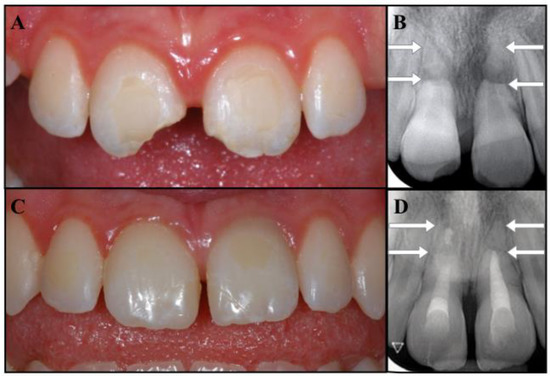

A 10-year-old Caucasian girl suffered combined injuries to both maxillary central incisors while skiing. At the moment of the traumatic event, her mother was able to collect the extruded portions of the two teeth and to perform the immediate repositioning of both segments. The patient was then taken to a general dentist to assess the status of the teeth involved in the accident. The patient’s medical history was noncontributory. Following the clinical examination, the dentist reported that teeth #1.1 and #2.1 had suffered extrusive luxation, had been replanted correctly, and that tooth #1.1 also had an enamel–dentin uncomplicated crown fracture, while tooth #2.1 exhibited a fracture limited to the enamel. Damages to the alveolar bone, or to the soft tissues, were not observed. The dentist applied a passive and flexible splint for 4 weeks; wire and composite stabilization were chosen so as to favor oral hygiene and because they are well tolerated. Furthermore, the dentist prescribed antibiotics (Amoxicillin with clavulanic acid, 1000 mg, twice a day, for one week) and advised the patient to take care of the injured teeth and to rinse with an antibacterial agent (chlorhexidine gluconate 0.12%). The dentist monitored the teeth, which remained asymptomatic, and nine months after the trauma the dentist referred the patient to an endodontist to check the pulpal status of the traumatized elements. During the consultation, the girl reported a mild tenderness to pressure on tooth #2.1. The soft tissues appeared healthy; the extruded teeth showed no signs of discoloration, grade 1 mobility, and a coronal fracture on both teeth. Tooth #2.1 was tender to percussion and palpation and did not respond to pulp sensitivity tests, while tooth #1.1 was slightly tender to percussion and did respond to sensitivity tests. Interestingly, the periapical radiographs showed the presence of a horizontal fracture of the apical third in both the avulsed teeth. The periapical area of the coronal fragment of tooth #2.1 showed a defined radiolucency, while no clear radiolucency was visible on the fractured portion of tooth #1.1 (Figure 1B).

Figure 1.

(A) Clinical photograph showing the uncomplicated crown fracture of the incisal third of teeth #1.1 and #2.1. (B) Periapical radiograph showing the apical root fracture of teeth #1.1 and #2.1 (arrowed) and the radiolucency at the fracture line of #2.1 (small arrow).

The diagnosis was as follows: apical horizontal root fractures of teeth #1.1 and #2.1; severe extrusive luxation of the coronal fragment of both central incisors, which were successfully repositioned; pulp necrosis and chronic apical periodontitis on the coronal portion of tooth #2.1; uncomplicated crown fractures of the incisal third of teeth #1.1 and #2.1. The residual apexes did not show signs or symptoms of apical periodontitis (Figure 1A,B). The prognosis was considered guarded. The proposed treatment was apexification on tooth #2.1 (as the fractured portion of the coronal fragment mimicked an open apex), restoration of the access cavity and of the crown fractures with bonded composite resin, and follow-up of the overall case. The patient and her parents were informed of the diagnosis, treatment plan alternatives, and prognosis of the teeth. Written consent was obtained, and the proposed endodontic management was accepted.